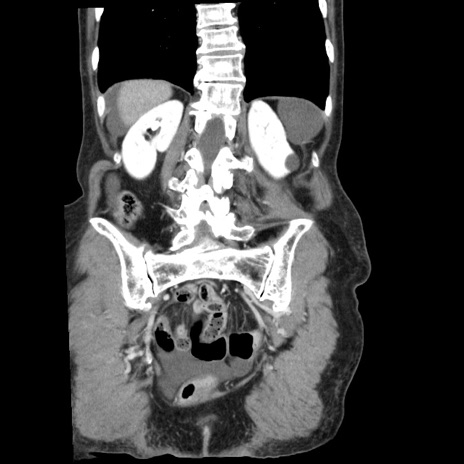

症例1(冠状断像)

【症例】80歳代女性

【主訴】腹痛

【現病歴】8時間前から腹痛あり来院。

【既往歴】糖尿病、脂質異常症、子宮体癌にて子宮全摘術

【身体所見】意識清明・会話良好だが腹痛で苦悶様、全腹部にわたって反跳痛と圧痛あり

【データ】WBC 13600、CRP 0.14、LDH 224、CK 90